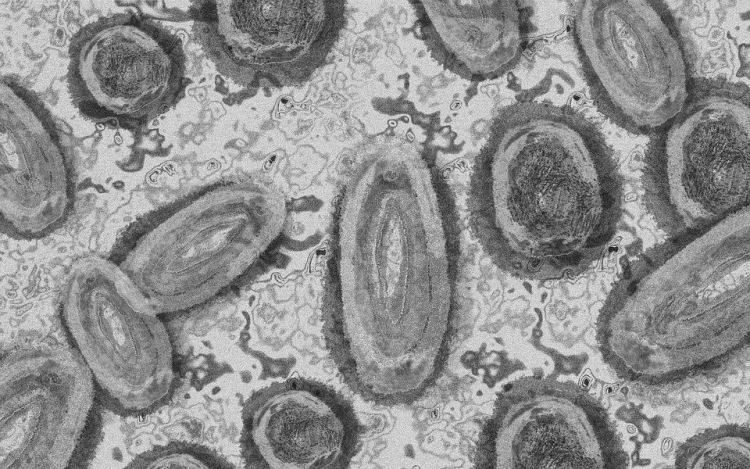

Tovább nőtt a majomhimlő-fertőzöttek száma Magyarországon

Újabb két embernél igazolt majomhimlő-fertőzést a Nemzeti Népegészségügyi Központ (NNK) a 33. héten - augusztus 15-től 21-ig -, ezzel 64-re nőtt a magyarországi esetek száma.

Az NNK pénteki közlése szerint a 22 és a 31 éves férfi általános állapota megfelelő, kórházi kezelés egyikük esetében sem szükséges; otthonukban tartózkodnak elkülönítve.

Az NNK korábban azt közölte, hogy a betegség általános, nem specifikus tünetekkel - lázzal, hidegrázással, izomfájdalommal, hátfájdalommal, fejfájással, fáradtsággal -, illetve a nyirokcsomók duzzanatával kezdődik, majd 1-3 nappal a bevezető tünetek után bőrkiütések jelennek meg. A kiütések sok esetben először az arcon, majd a tenyéren és a talpon fordulnak elő, de megjelenhetnek a szájnyálkahártyán, a nemi szerveken és a végbél környékén is.